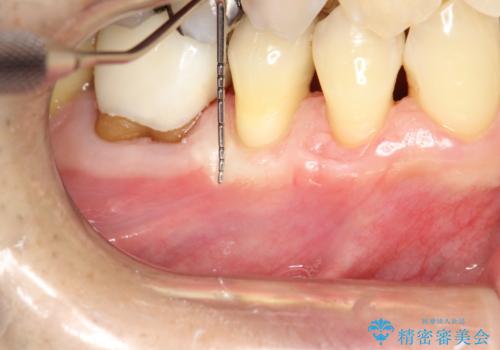

術式は歯冠側移動術と歯肉結合組織移植術を併用しました。

今回のケースでは小臼歯2本分の幅に渡って丈夫な歯肉を確保させるため、オペのデザイン上、横に幅広く均一な結合組織を採取する必要がありました。そのため、トラップドア方式で内部の組織をえぐって採取する術式は使わず、上顎歯肉の表層から結合組織部までを含む部分までを遊離歯肉採取の要領でやや深めに採取し、表層部分をトリミングする事で均一な厚みの結合組織を採取しました。この術式の利点として、上顎の歯肉に過度に深い侵襲を与える事がないため、組織採取部の術後の治癒が非常に早く、術後の不快症状も少なくて済む事が挙げられます。